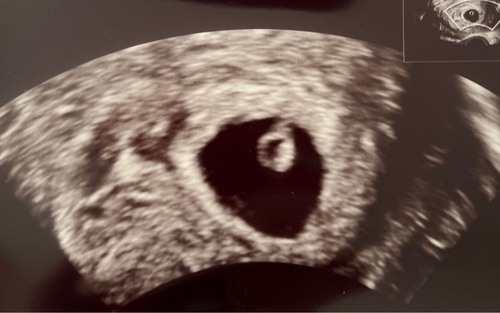

Hoera! We hebben een goede echo met een hartslag ❤️